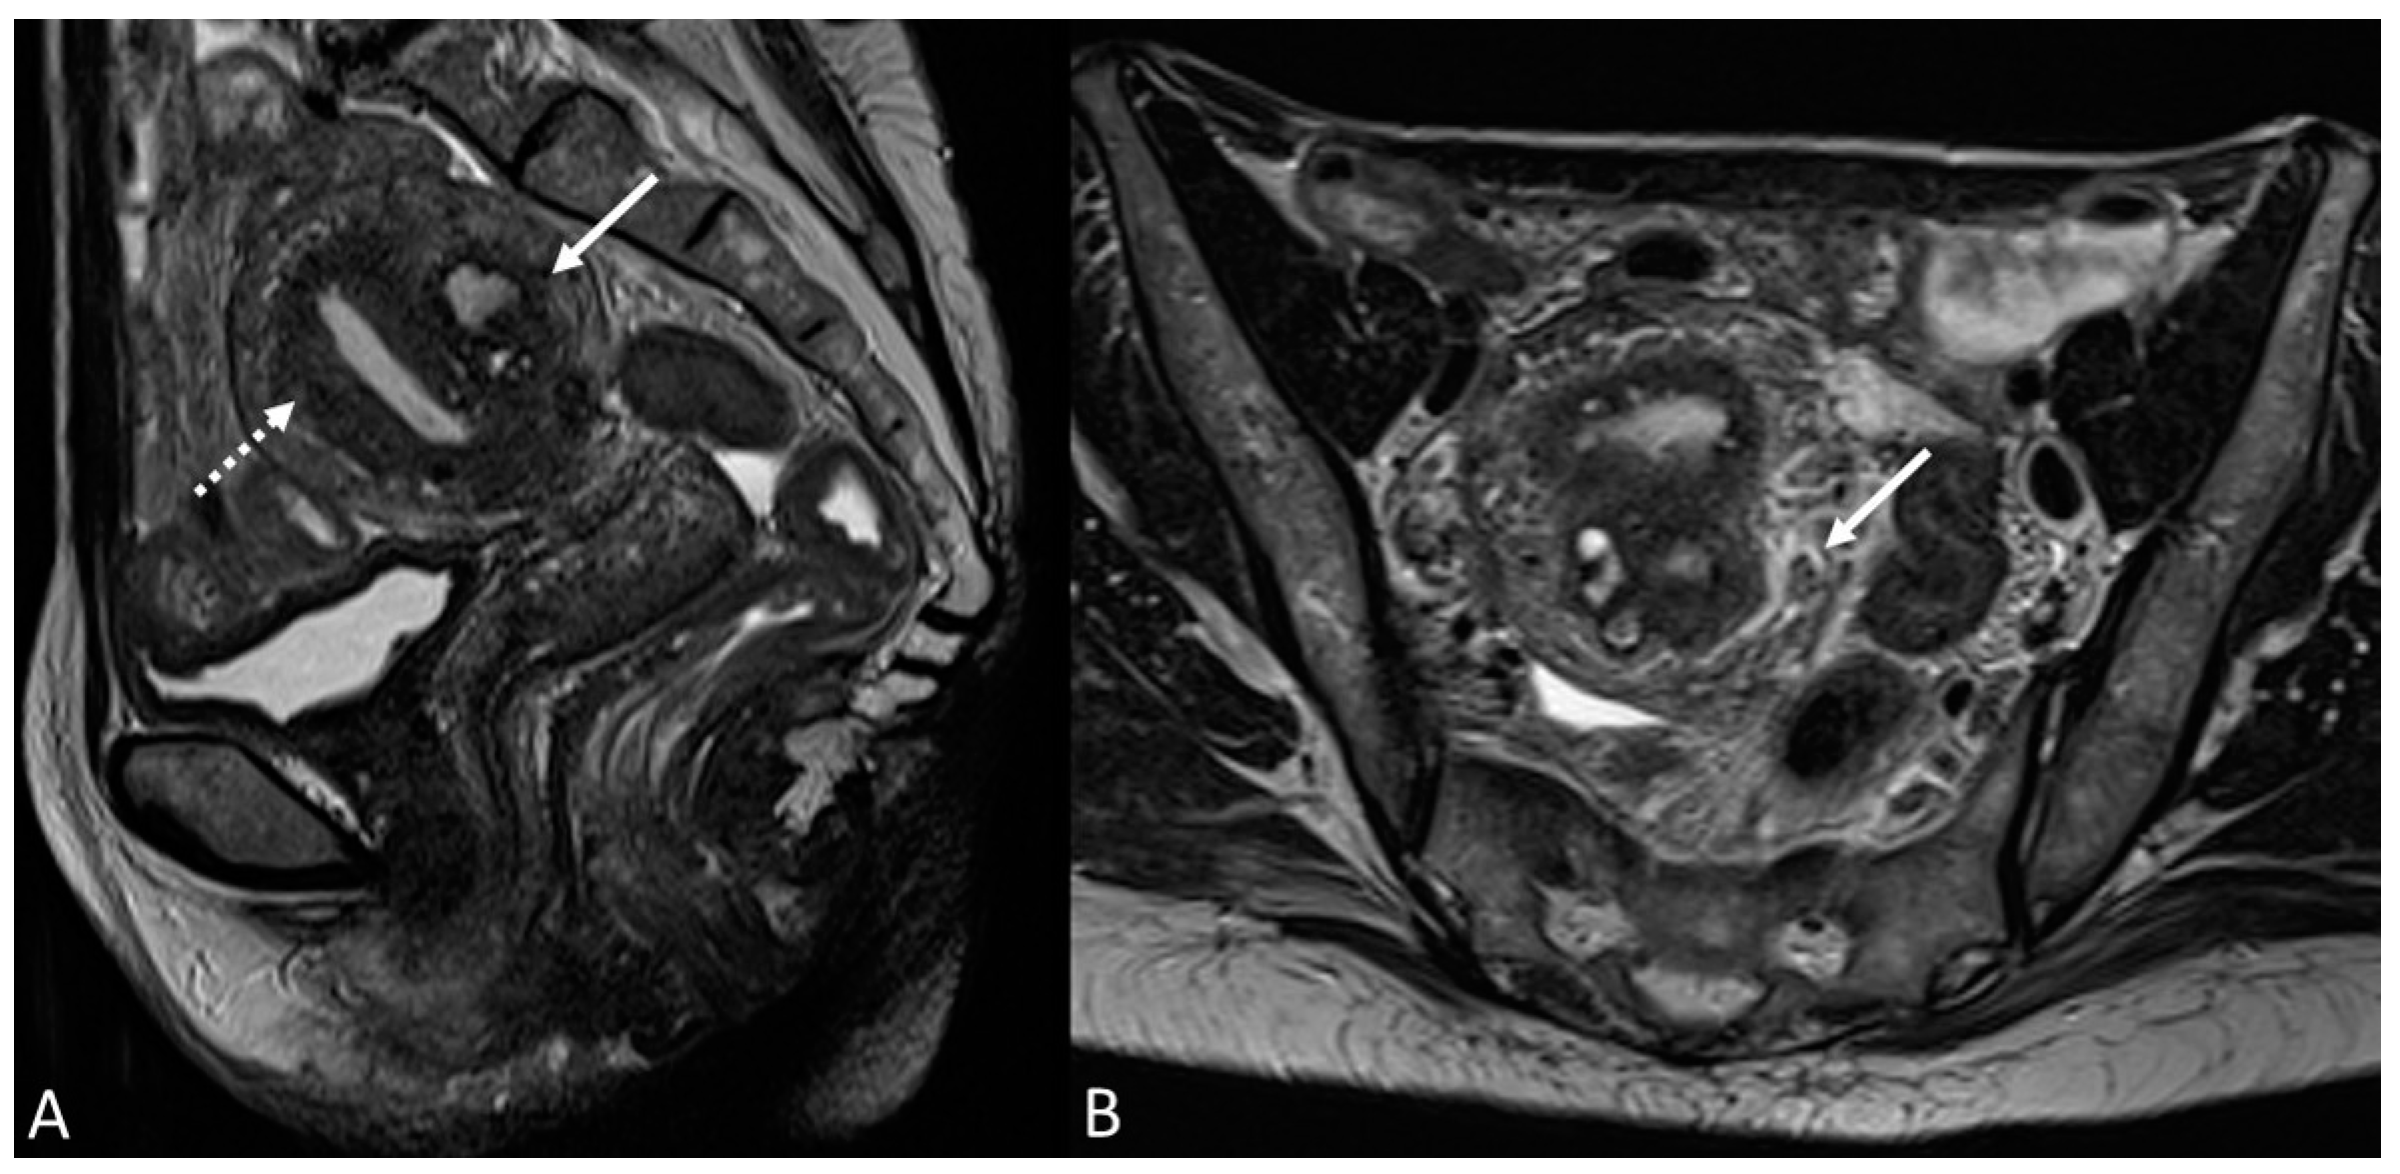

In other cases, the involvement of the round ligament can be appreciated as irregular contours with a nodular aspect [43] (Figure 2).

Figure 2.

Deep infiltrating endometriosis of the anterior and posterior compartments in 33-year-old female with dysmenorrhea, chronic pelvic pain, dyspareunia and dyschezia. (A) Sagittal T2WI. Evidence of external anterior adenomyosis and plaque of the vesico-uterine pouch (white arrow); (B) Sagittal T2WI. Retrocervical localization of DIE (white arrow); (C) Axial T2WI. Left uterosacral ligament (USL) localization (white arrowhead), plaque of vesico-uterine pouch (white arrow) with involvement of the round ligaments, particularly on the left (white dotted arrows), and adhesions with the ovaries (retraction of the broad ligaments).

Involvement of the proximal portion of ligaments (distance less than 2 cm from the cervix) may, in some cases, be associated with thickening at the level of the torus uterinus; in such cases, it is essential to report any mass or thickening in the upper portion of the posterior cervix, as this could cause the surgeon to proceed with a laparoscopic trans-vaginal approach [7] (Figure 2, Figure 3 and Figure 4).

Figure 3.

Right uterosacral ligament localization in a 43-year-old female. The right uterosacral ligament appears thickened at uterine insertion (white arrow).

Figure 4.

Retrocervical endometriosis plaque, intestinal localization, kissing ovaries with bilateral ovarian endometriomas. (A,B) Axial T2WI; (C) Coronal T2WI. Hypointense retrocervical plaque (white arrowhead in (A)) localized in the uterine torus with involvement of the utero-sacral ligaments. Adhesions involve both ovaries with bilateral endometriomas (white arrows), which are prolapsed in a retro-uterine position and adhered to the utero-sacral ligaments and the recto-sigmoid junction. There is also an eccentric anterior parietal thickening in the recto-sigmoid junction suggestive of intestinal endometriosis lesion (white dotted arrow in (A)).